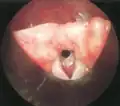

Subglottic stenosis is graded according to the Cotton-Myer classification system from one to four based on the severity of the blockage. Grade 1 is up to 50% obstruction, Grade 2 is 50-70% obstruction, Grade 3 is 70-99% obstruction, and Grade 4 is with no visible lumen.[5]

Grade 1 subglottic stenosis

Grade 1 subglottic stenosis Grade 2 subglottic stenosis

Grade 2 subglottic stenosis Grade 3 subglottic stenosis

Grade 3 subglottic stenosis Grade 4 subglottic stenosis

Grade 4 subglottic stenosis